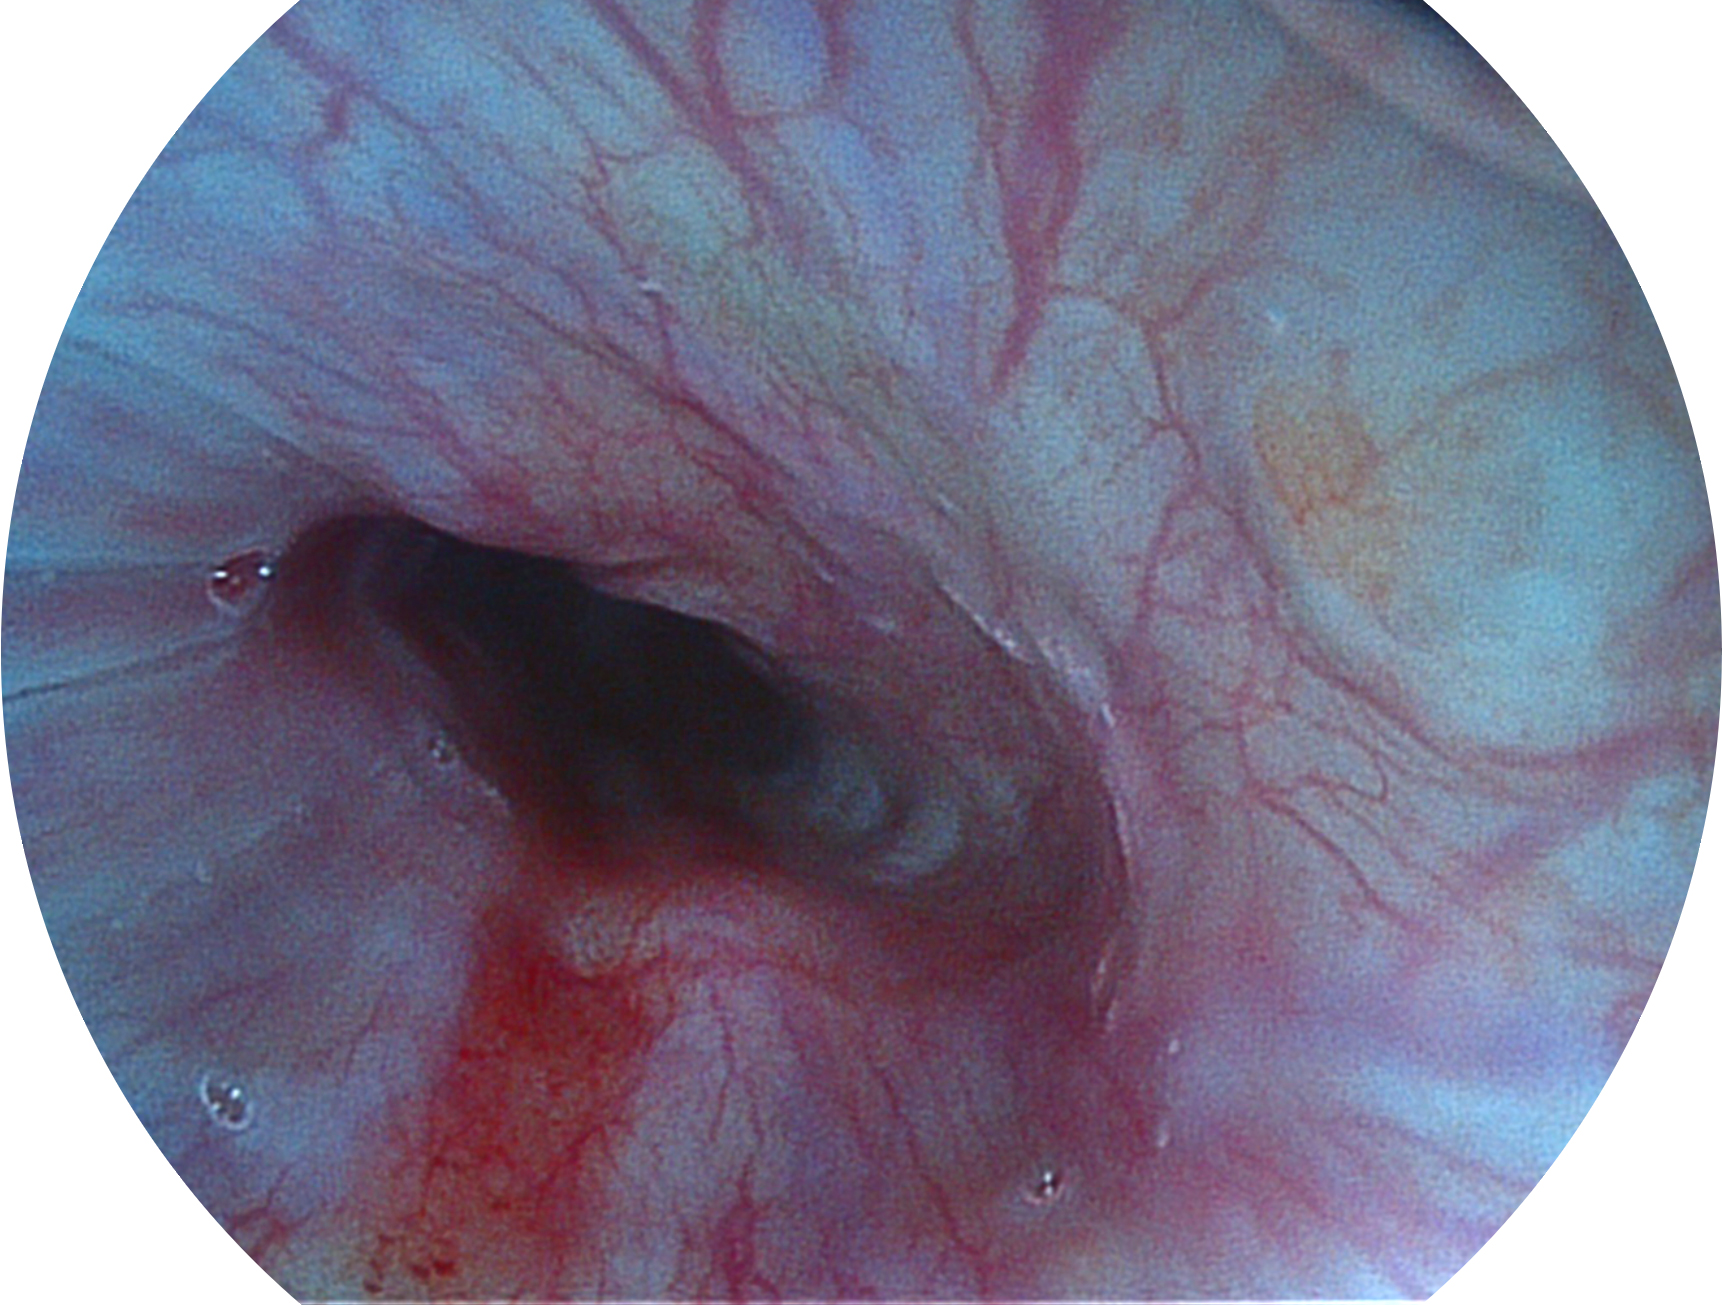

SFI技术是结合特定光谱照明与数字光谱滤波,实现高亮度特殊光成像。染色模式下,不改变粘液、食物残渣、粪液等基本颜色,在保持与白光照明相似的图像色调的同时突显了图像颜色的红白对比度,且在远距离观察的情况下具备与普通白光模式相同的图像亮度,有助于消化道疾病的大范围扫查和早癌筛查。

• 白光图像 SFI图像